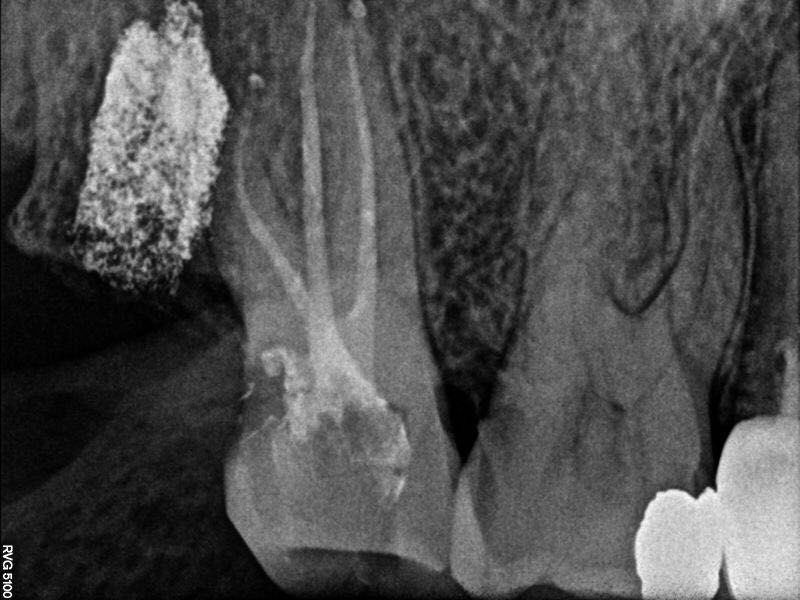

根充片

面对重度弯曲的根管,手用器械有时根本下不去,本病例运用手用锉疏通至10#换pathfile锉,之后用PROTAPER NEXT备根管,镍钛器械最大的优势就是能尽量保证根管形态,不易将弯根拉直及形成台阶,提高工作效率